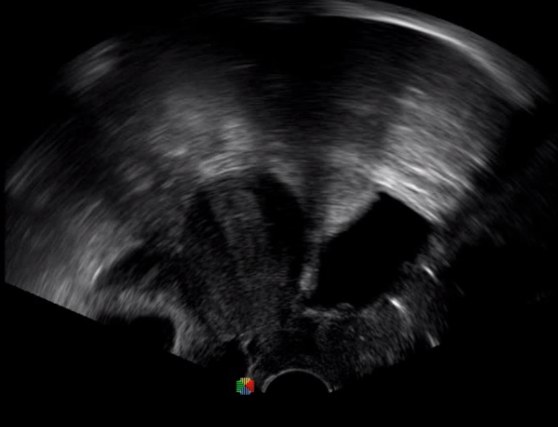

多數(shù)的生殖科醫(yī)生對于受精卵的植入采用憑經(jīng)驗操作或是使用傳統(tǒng)腔內(nèi)探頭引導(dǎo),同樣存在手術(shù)空間小、受精卵放置位置不確定等風(fēng)險。專業(yè)的宮腔專用探頭,配合專用的窺器使用,為醫(yī)生提供最大的手術(shù)視野。

胎移植臨床圖